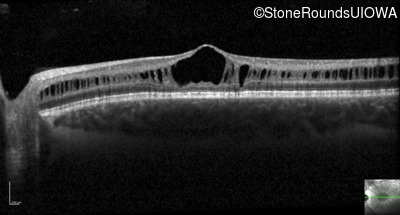

Optical Coherence Tomography - Left - 20/50

Exemplar / OCT Stack

OCT Stack